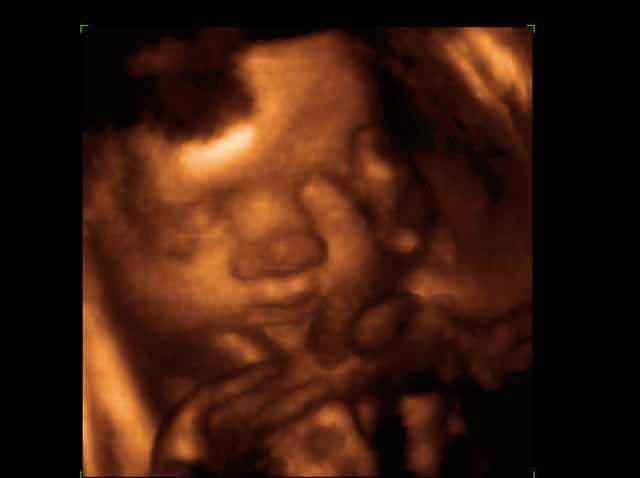

3D Fetal Face Ultrasound Scan Photos